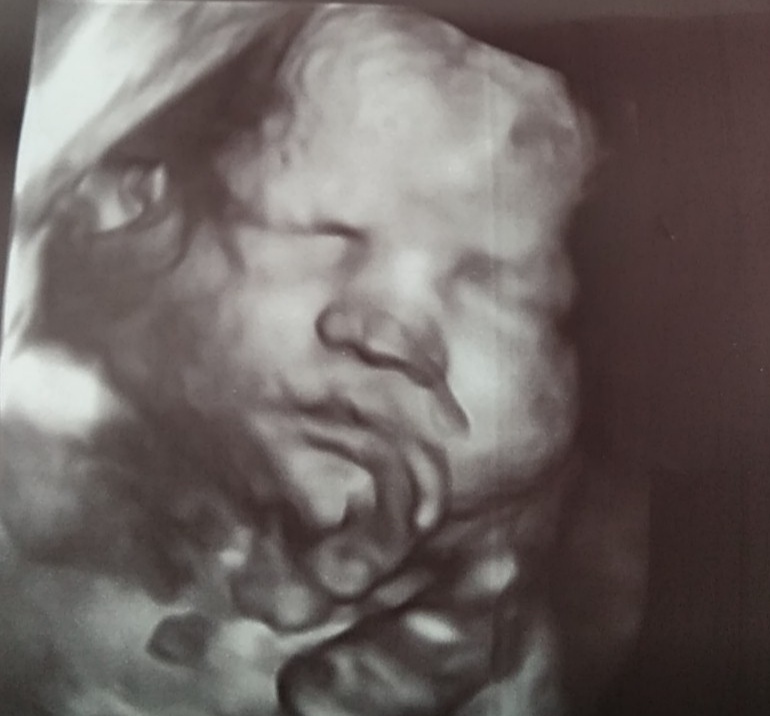

Сходила на УЗИ. Малышка весит 2200. По всем замерам также отстаём на недельку. Доплер в норме. И была удивлена, что бонусом сделали несколько фото в 3д. Очень похожа на младшего сына.

И я жадная) тк делаю УЗИ часто. оплатила просто УЗИ, а 3д оказалось бесплатным бонусом, даже 4д - в движении. И ещё долго ловили ракурс. В другом месте тоже 3д включают просто так, но если сразу не видно личико, то и не пытаются поймать.